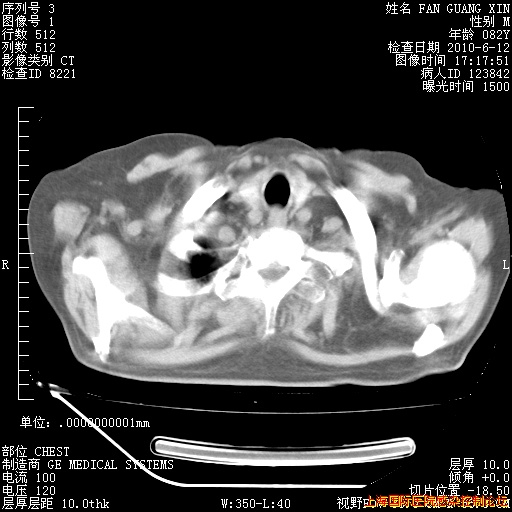

补发6月12日肺部CT肺窗

6月12日肺窗